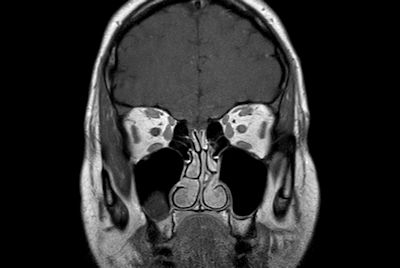

High quality orbit imaging